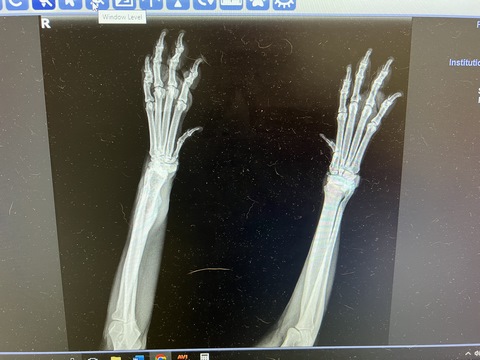

Tank was really happy with a full house.  Unfortunately, he's had some new issues with his health.  After developing diabetes in April, we finally appeared to have him stabilized and on a good dose of insulin.  But, he has been limping and had a swollen leg for a bit.  We took him into the vet several weeks ago and they provided some anti-inflammatory pills.  While it appeared to help for a week or so, the swelling came back quickly.  So, Alexa took him to another vet appointment just before we left for Greece.  The news was not good.  It is likely bone cancer.  The radiologist said it looked more like an infection (which is possible with his diabetes).  While the vet said that was unlikely, she did prescribe some antibiotics and we made an appointment with the oncologist for when we got back from our trip.  By then, Dog Tales reported he was really no longer putting weight on the leg.  The next appointment confirmed the bone cancer and he was quickly scheduled to have the limb amputated.